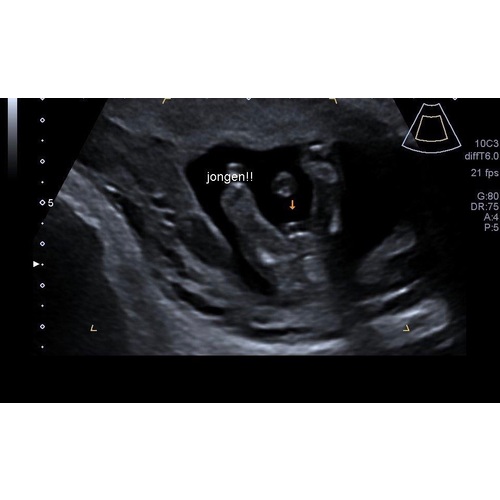

Echo met 14 weken, jongetje ( al ben ik zelf nog wat sceptisch omdat het zo vroeg was ) 🙈

Reactie op mamavan3kids

Echo met 14 weken, jongetje ( al ben ik zelf nog wat sceptisch omdat het zo ...

Ooh maar deze is wel duidelijk idd